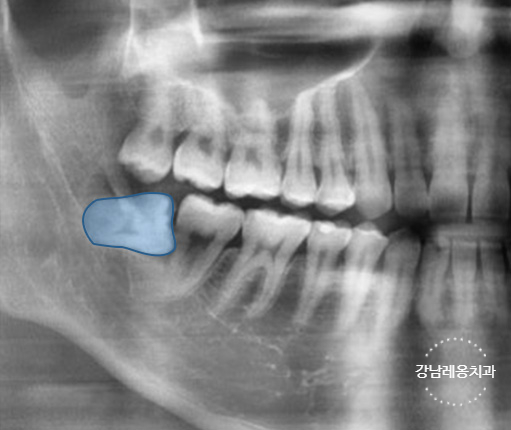

✅ 잇몸 속에 완전히 묻혀 있는

완전 매복 사랑니

✅ 옆으로 누워있는 수평 매복 사랑니

고난도 케이스 경험 다수

최소절개

하루 발치 최대 60개

사랑니 발치로 강남레옹치과에 방문해주시는

40~50%가 수평/매복 사랑니이며

아래와 같은 고난도 케이스도

충분한 상담을 통해

사랑니 진료를 진행하고 있습니다.